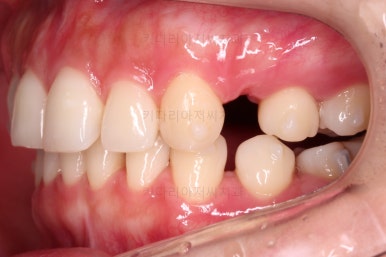

공간, 교합, 중앙선 모두 매우 좋아지고 있습니다.

윗니 한 쪽만 왜소치여서 100% 중앙선을 못맞추는 건 환자분 본인도 잘 아시는데요.

그래도 할 수 있는데까지 해보기로 했습니다.

중앙선도 처음보다 매우 좋아진 양상입니다.

옆모습도 큰 변화없이 양호하게 진행중이고요.